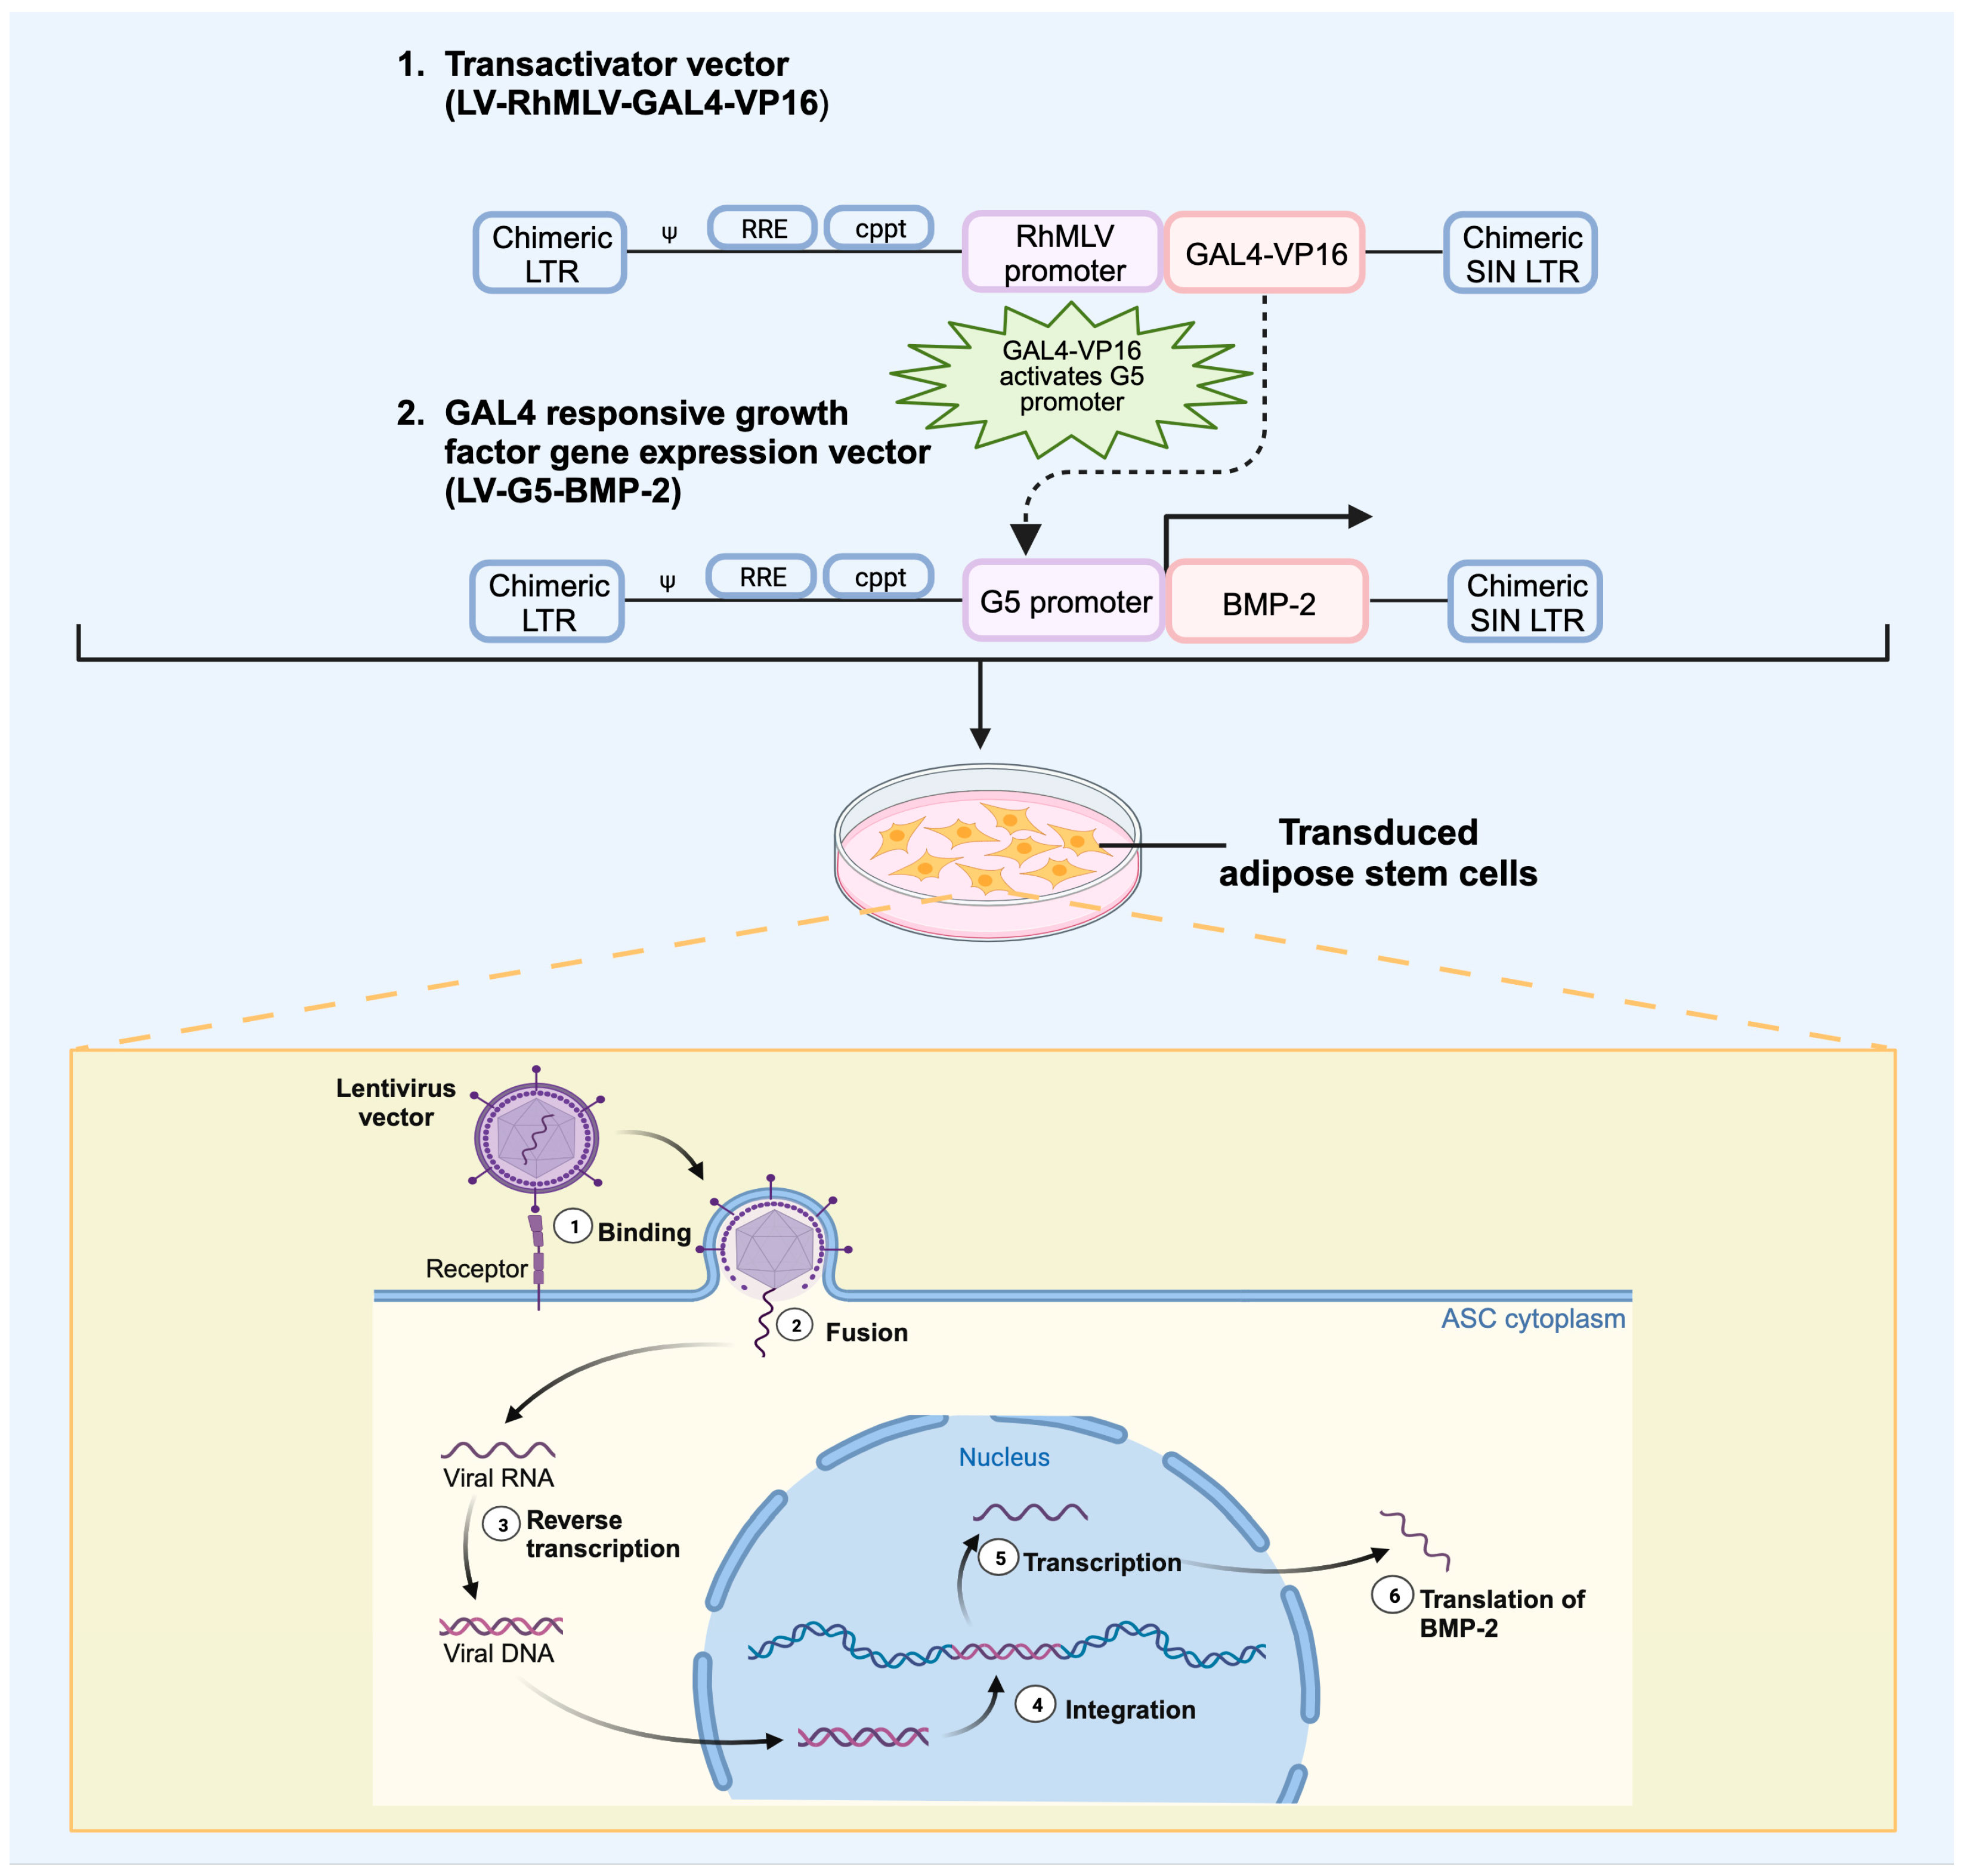

4. Role of Regional Gene Therapy in Growth Factor Delivery

4.1. In Vivo Versus Ex Vivo Regional Gene Therapy

4.2. Viral Vectors

Viral Vector Delivery of Growth Factor in Bone Repair